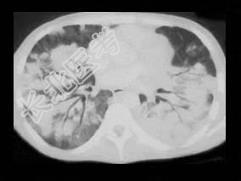

- 单项选择题男,27岁, 干咳,呼吸困难半月余, 有艾滋病病史半年余,请结合CT检查, 选出最可能的诊断 ( )

A、粟粒型肺结核

B、弥漫型肺癌

C、间质性肺炎

D、矽肺

E、Kaposi肉瘤